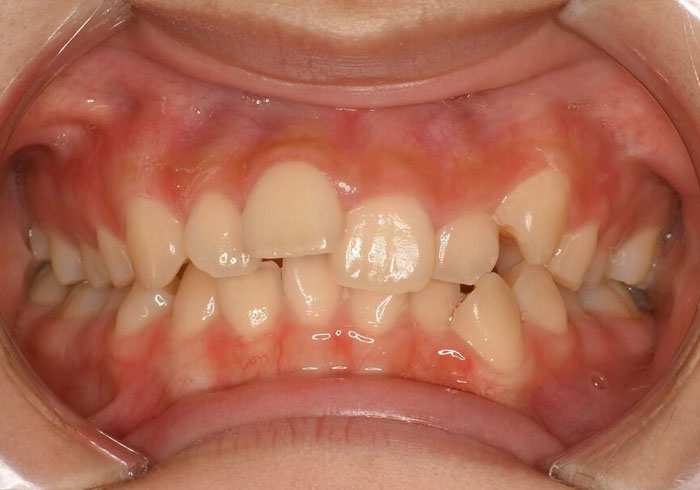

治療前

マウスピース矯正 マウスピース矯正 マウスピース矯正